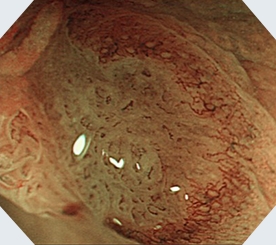

大腸内視鏡検査(大腸カメラ)は、大腸(結腸と直腸)の内部を観察する事が可能です。

内視鏡という柔軟な管状の検査器具を利用し、肛門から挿入して大腸の内部を直接視覚的に確認します。内部の映像をリアルタイムでモニターで確認することで、必要に応じて生検(組織の一部を採取して病理検査を行うこと)やポリープの摘出などの治療的な処置を行います。

大腸内視鏡検査は、大腸の異常や病変の早期に発見、特定する事に役立ち、大腸ポリープや腫瘍の検出、炎症や潰瘍の有無の確認、出血の原因の特定をはじめ、スクリーニングや予防目的として、大腸内視鏡検査は大腸がんの早期発見を目指します。

症状のない微小な大腸ポリープやがんを発見することができます。